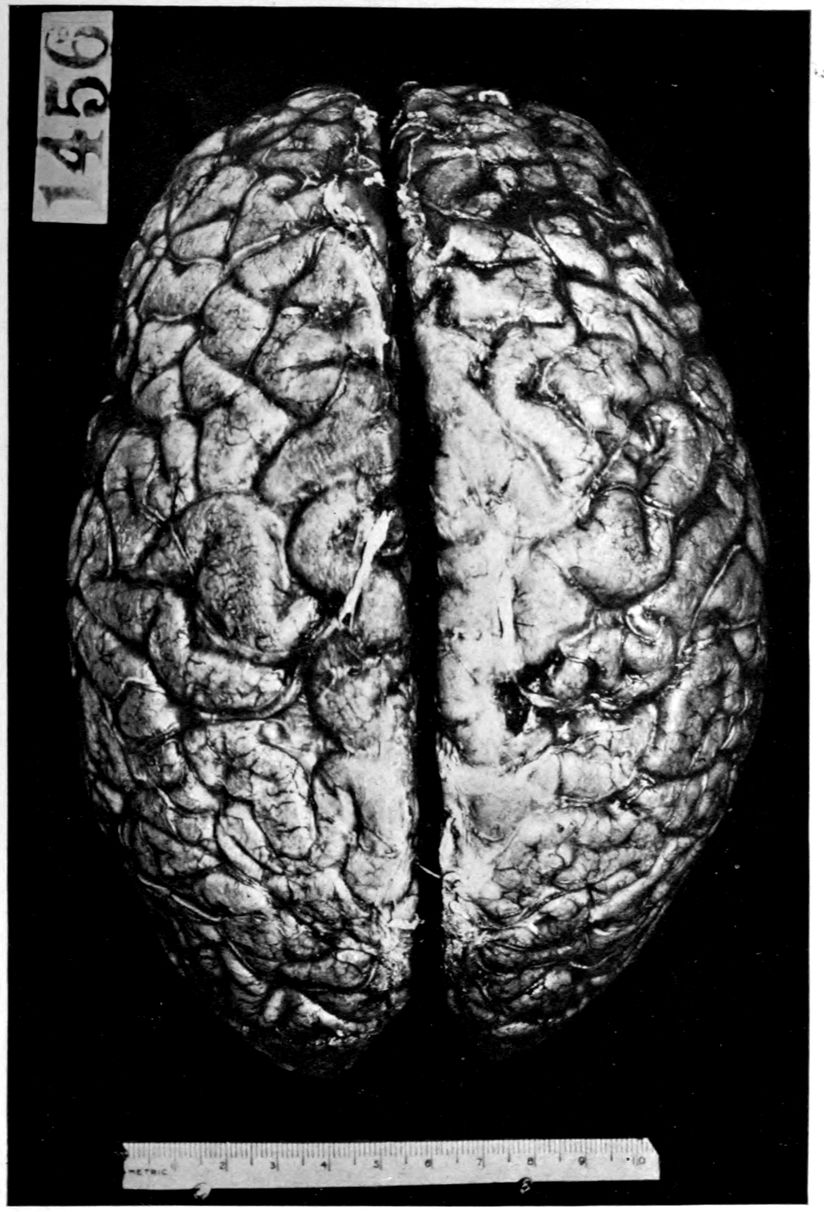

Brain weight, 1265 grams. Consistence somewhat increased throughout and somewhat evenly increased. The prefrontal region shows the maximal increase of consistence but the remainder of the frontal region and corresponding occipital region are much firmer than normal. The two superior temporal gyri appear to be firmer than adjacent gyri and are possibly slightly diminished in superficial diameter. The hippocampal gyri are fairly firm. The substance on section is a trifle more moist than normal. The gray and white matter cut quite evenly. Diminution in depth of gray matter, if existent, could not be demonstrated. The ventricles show a moderate sanding throughout, best marked in the fourth ventricle. The basal ganglia are not remarkable except for the development of numerous dilated perivascular spaces about the lenticulostriate vessels. The pons is atrophic, but more so on the right side. The pons, like the prefrontal cortex, shows on section a distinct increase of consistence immediately beneath the pia mater. The white bands of the pons on section are distinctly firmer than the intervening substance. The olives are of equal consistence. Weight of cerebellum, pons, and medulla, 155 grams. The cerebellum shows an obvious atrophic and gliotic process of a symmetrical character. The superior surface, including both vermis and hemispheres, shows a consistence above normal and general reduction of the depth measured from the white matter. The reduction in depth gives rise to a visible depression as compared with tissue posterior to the postclival sulci. The lobus cacuminis, though slightly raised from the surrounding lobes, is equally firm, if not firmer. The superior and inferior surfaces show practically an equal increase of consistence. The dentate nuclei are not especially increased in consistence. The flocculi are reduced in size about one-third.

Parenchymatous losses have led to Atrophy and Sclerosis, of very varying extent in different parts of the encephalon. The atrophy is characteristic in paretic neurosyphilis, but by no means constant. Numerous cases have come to autopsy without clearly defined gross atrophy. Sclerosis is also characteristic and even more frequent than atrophy, doubtless because sclerosis represents an earlier phase of a process eventuating in gross atrophy.

Vascular neurosyphilis—effects of syphilitic thrombosis of Sylvian artery 10 years before death. (Case 4.)